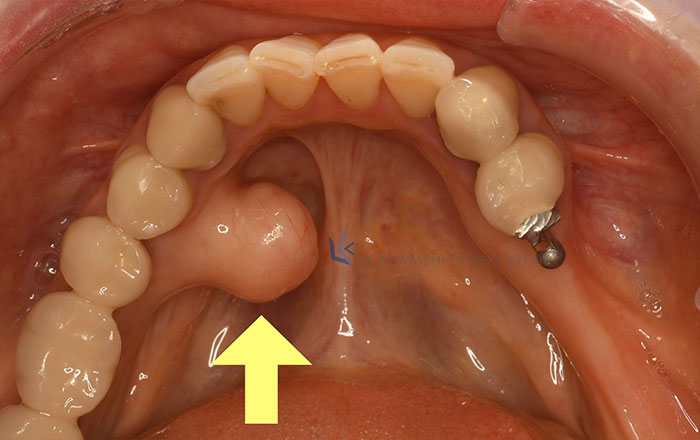

2)骨隆起

骨隆起とは、歯ぐきにできる硬い出っ張りです。

歯ぎしり・食いしばりがあると、上顎や下顎に、骨隆起という白いこぶのような出っ張りができることがあります。

歯ぎしりや食いしばりをすると、歯ぐきにとても強い力がかかります。

強い力から歯ぐきの骨を守るために、上下の歯ぐきの骨が接触する部分が過剰に発達して、骨隆起ができると言われています。